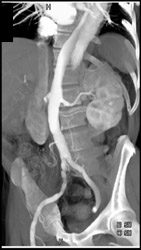

Aortic Dissection